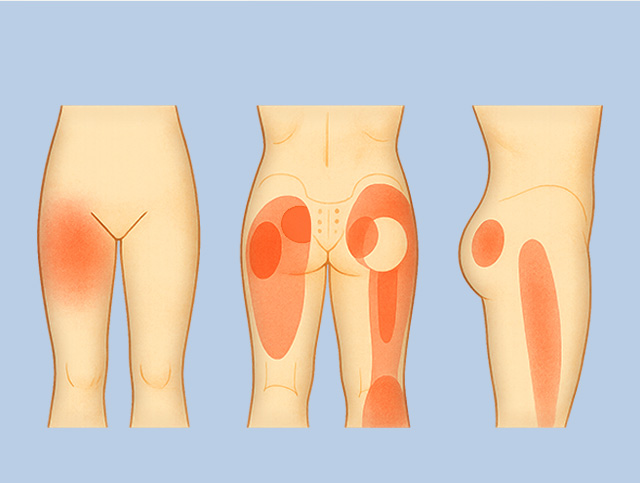

좌골신경통

좌골 신경에 염증, 손상, 압박이 발생하여 허벅지, 종아리, 발로 이어지는 통증

허리디스크나 척추관협착증, 이상근 증후군이나 근근막통증 증후군에 의한 발생이 많은 편

허리에서 발까지 연결되는

좌골신경의 염증, 손상에 의한 통증 치료

디스크, 협착증 같은 요추질환의 방사통에

의한 엉치와 다리 통증, 저림, 감각 이상도

의학 · 한의학의 통합적 치료

엉덩이와 허벅지 근육의

피로, 염증, 손상에 의한 통증도

근본적 치료 도모